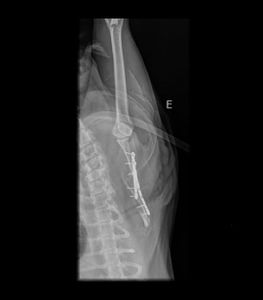

Oi gente, essa é minha gatinha Shabyska. Minha companheirinha, que ficou comigo por quase 10 anos, mas infelizmente foi atacada por cães, teve várias perfurações pelo corpo, trauma na mandíbula e fratura na escápula. Ela teve que passar por cirurgia para a colocação de duas placas na escápula e sonda esofágica para alimentação, pois não conseguia mover a mandíbula. Cinco dias após o procedimento anterior, ela apresentou um quadro de dificuldade respiratória o que a levou a ter de fazer uma cirurgia de herniorrafia diafragmática, mas no pós operatório ela teve uma descompensação respiratória e infelizmente veio a óbito. Perdi minha Shabyska e preciso da sua ajuda para pagar as despesas médicas pois ficaram altissimas e infelizmente não estou conseguindo arcar com tudo sozinha, além de não ter obtido ajuda do responsável pelos cachorros.Você pode me ajudar? Obrigada!